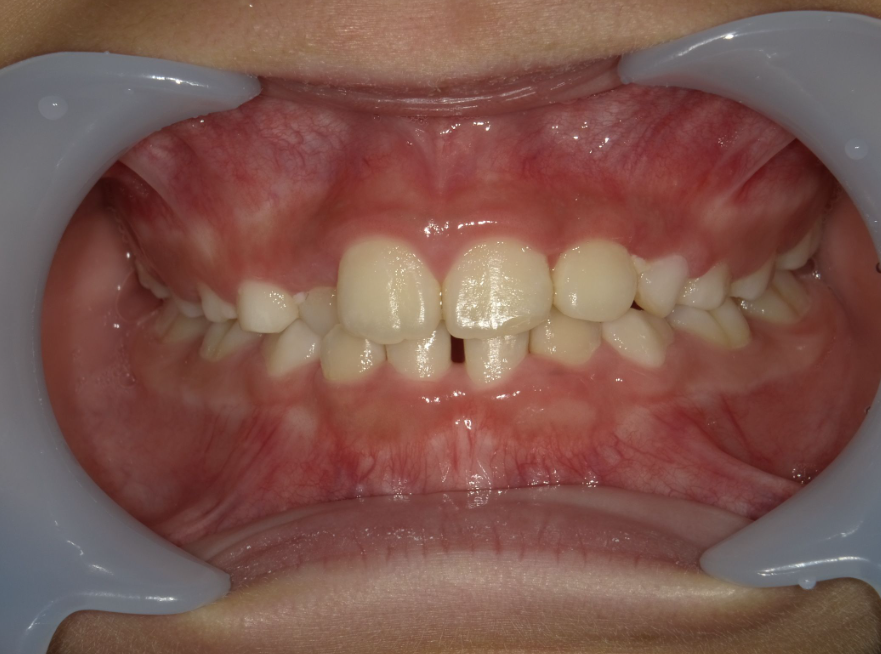

正面

| 治療内容 | インビザライン・ファースト |

| 治療詳細 | スペース不足や交叉咬合を整えるために、歯の表面にアタッチメント(白い突起)をつけ、治療を行いました。 |

| 患者情報 | 9歳 男性 予防矯正から移行 |

| 主訴 | 永久歯は生えそろう十分なスペースがない 一部分だけかみ合わせが反対 |